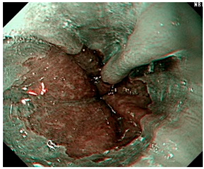

![]() | LA grade C–D | LA grade C–D | LA grade C–D |

| Image | GERD Endoscopy Grading | Gerd-VGGNet | GerdNet-RF |

|---|---|---|---|

![]() | LA grade A–B | LA grade C–D | LA grade C–D |

![]() | LA grade A–B | LA grade C–D | LA grade A–B |